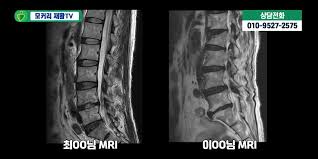

🩻 진단 방법

- MRI: 신경압박 정도, 협착 위치·범위 정확하게 파악

✅ 치료 방법

- 보존적 치료에도 증상 지속 시 고려